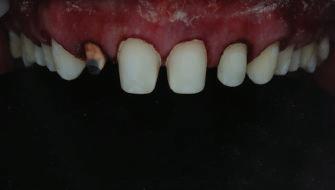

Пациентът постъпи в клиниката с молба за тотална рехабилитация на усмивката. Той не харесваше централ ните си резци, които според него бяха твърде къси и квадратни. Имаше раз стояние от медиално и дистално на латералните му резци. Друго сериоз но оплакване бе свързано с металоке рамичната корона на зъб 12, която бе жълтеникава и неестетична, като цяло не харесваше вида на венците си и както самият той се изразяваше, „вижда се прекалено много от венците при усмивка“.

След диагностиката бяха направени екстра- и интраорални снимки, както и рентгенографии; професионалното почистване бе от изключителна важ ност, бяха дадени и инструкции за лич на орална хигиена. Бе направено интра орално сканиране с Medit i500. Цялата тази информация бе използ вана в приложението Smilecloud за 2D биометричен дизайн. В приложението са налични естест вени форми на зъбите и щом бяха под брани зъби и бе направен дизайн

Препарираните зъби бяха импорти рани в Exocad и насложени върху ес тествените форми от биометричния дизайн, като така стана ясно дали зъ бите са били препарирани коректно. По този начин зъболекарят и зъботехни кът работят в една и съща екосистема и резултатът е оптимален. С короната се справихме чрез диги тална редукция на циркония в Exocad, като по този начин на практика създа дохме циркониево кепе, след което про изведохме фасета от IPS Empress Cad Multi. Кепето от Katana Zirconia на зъб 12 с букално послойно нанесена керами ка бе фрезовано (послойното нанасяне бе направено, за да се подобри връзката и да се осигури адхезивно циментиране на фасетата към циркониевото кепе, както и за да се напасне цветът към този на съседните зъби). При първото сканиране регистрирах ме цялата горна зъбна дъга, така че, ко гато се наложи да сканираме повторно, бе изтрит и сканиран наново само зъб 12, тъй като венците не бяха отдръп нати при второто сканиране.

Една седмица след препарацията на зъбите и циментирането на цирко ниевото кепе бяха изработени 12 IPS Empress Cad Multi фасети. Макро- и микротекстурата на фасе тите бяха направени на ръка, след кое то бяха нанесени 3D характеризации с боички, а полирането отново бе напра вено ръчно, за да им се придаде естест вен и естетичен вид. Предизвикателството тук беше короната да има същите оптични характеристики като тези на остана лите зъби при естествена светлина, през поляризационен и флуоресцентен филтър. 3D принтерът бе Fromlabs, софтуерът за фрезоване – Mill Box, а фрез апаратът –imes icore CORiTEC 350i. В крайна сметка постигнахме ес тествен вид на усмивката с натурал на зъбна морфология при изцяло диги тален протокол, при който дизайнът бе направен първоначално и през всич ки етапи на лечението се придържахме към него до самия край Излишно е да отбелязваме, че всички сме удовлетворени от постигнатото! Преди След Победител в категория „Клиничен случай с изцяло дигитален протокол“ в конкурса „Усмивка на годината 2022“